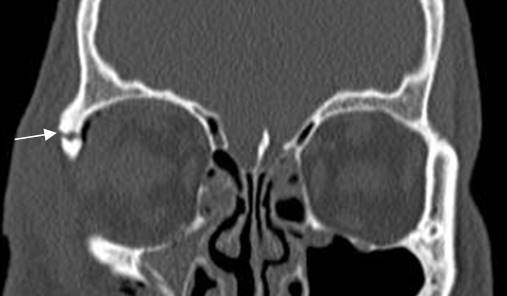

Fig 215 A. Fractura de órbita, sin atrapamiento muscular.

A y B: TAC reconstrucción coronal. Fracturas no deprimidas en el piso de la órbita y sin signos de atrapamiento muscular.